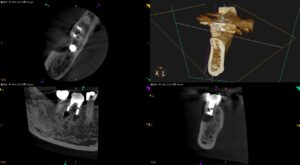

Apicoectomy時にはApexの位置を正確に把握する必要がある臨床的理由〜#30 Crown, Post Core removal⇨M,D Apicoectomy 1回法

紹介患者さんの治療。 主訴は、 右下のインプラントの隣の歯の根の先に病気があり、このままだとインプラントに影響があると言われた。インプラントはお金がかかったので何とか治療して悪い歯を直してインプラントを守りたい。 である … 続きを読む Apicoectomy時にはApexの位置を正確に把握する必要がある臨床的理由〜#30 Crown, Post Core removal⇨M,D Apicoectomy 1回法